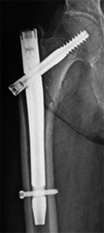

骨折の中でも特に多いのは、骨折後の寝たきりの原因にもなる股関節周囲の骨折(大腿骨近位部骨折)で、その発生頻度の増加は2040年頃まで続くと予測されています。

寝たきりを防ぐためには早期の手術とリハビリが重要であり、当院でも積極的に取り組んでおります。高齢者の骨折患者様の多くは、骨が弱くなっている骨粗鬆症の状態です。

大腿骨近位部骨折(あしの付け根の骨折)

高齢者の転倒で生じる骨折の中でも頻度が高い骨折です。

寝たきりの原因としての頻度が高く、早期の手術とリハビリが望ましいものです。

• 画像:大腿骨近位部骨折

(術前)

(術後:ガンマネイル)

• 画像:骨折観血的手術(大腿)ガンマネイル

骨折観血的手術(大腿)

ガンマネイル